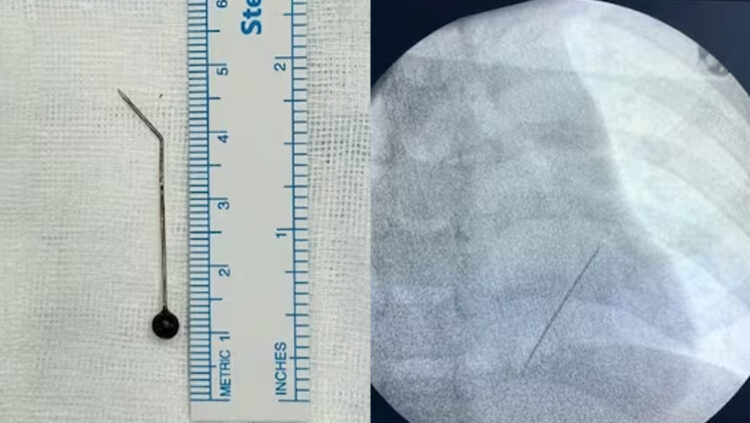

എക്സ്റേയിൽ ഇടതുവശത്തെ ശ്വാസകോശത്തിന്റെ ഏറ്റവും അടിത്തട്ടിൽ ലോവർ ലോബിനോട് ചേർന്ന് പിൻ കിടക്കുന്നതായി കണ്ടെത്തി. ഹൃദയത്തിലേക്കുള്ള പ്രധാന രക്തക്കുഴലുകൾക്ക് അടുത്തായാണ് സൂചി കിടന്നിരുന്നത്. അതിനാൽ തന്നെ അത് പുറത്തെടുക്കുക എന്നത് ശ്രമകരമായിരുന്നു.

കൊച്ചി അമൃത ആശുപത്രിയിൽ ചീഫ് ഇന്റർവെൻഷണൽ പൾമണോളജിസ്റ്റ് ഡോ ടിങ്കു ജോസഫിന്റെ നേതൃത്വത്തിലാണ് കുട്ടിയുടെ ശ്വാസകോശത്തിൽ കുടുങ്ങിയ 5 സെന്റിമീറ്ററോളം നീളമുള്ള സൂചി മൂന്നരമണിക്കൂറോളം നീണ്ട റിജിഡ് ബ്രോങ്കോസ്കോപിയിലൂടെ പുറത്തെടുത്തത്.